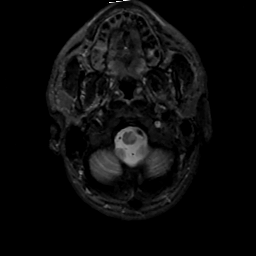

MR Study #2, February 17, 1991 -- Slice #3

[Home][Help][Clinical][Tour 1][Tour 2] Slice 3